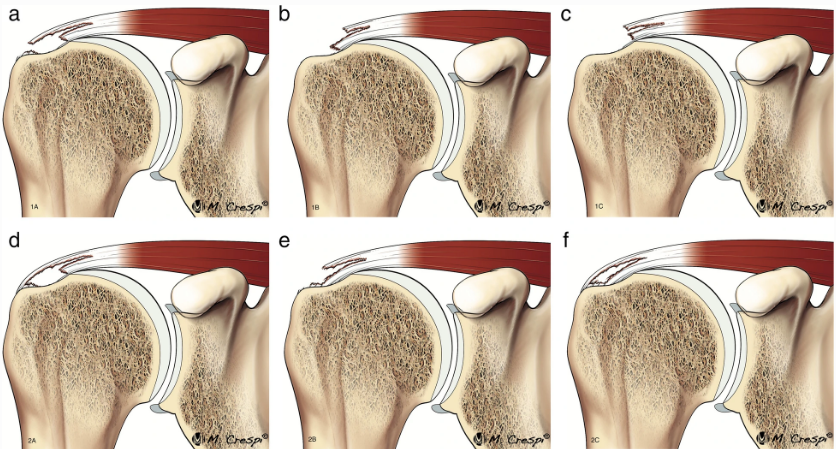

3. Tipos de Lesões do Manguito Rotador

As lesões do manguito rotador podem variar em gravidade, desde pequenas inflamações até rupturas totais dos tendões. Elas são classificadas em três categorias principais:-

- Ruptura do Manguito Rotador – Essa lesão pode ser parcial ou completa e, geralmente, resulta de trauma agudo (como uma queda) ou do desgaste progressivo ao longo dos anos. As rupturas completas podem exigir intervenção cirúrgica para reparo.